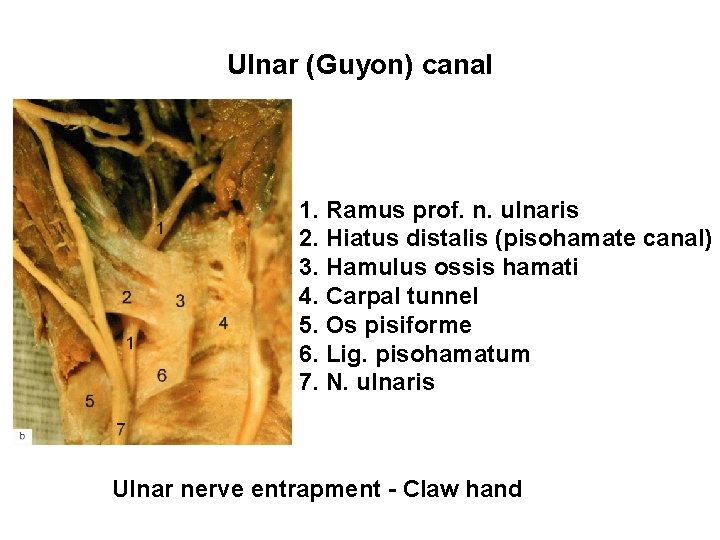

Ulnar (Guyon) canal 1. Ramus prof. n. ulnaris 2. Hiatus distalis (pisohamate canal) 3. Hamulus ossis hamati 4. Carpal tunnel 5. Os pisiforme 6. Lig. pisohamatum 7. N. ulnaris Ulnar nerve entrapment - Claw hand

Claw hand